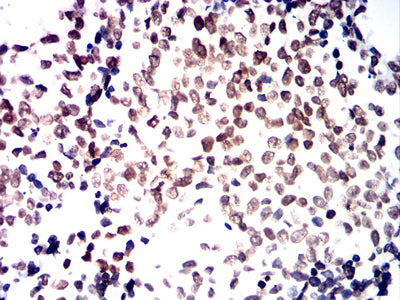

![HNF4A Mouse mAb[63743]](https://img1.dxycdn.com/p/s14/2025/0922/772/6560769447345699691.jpg)

Immunohistochemical analysis of paraffin-embedded human colon cancer tissues using HNF4A mouse mAb with DAB staining.